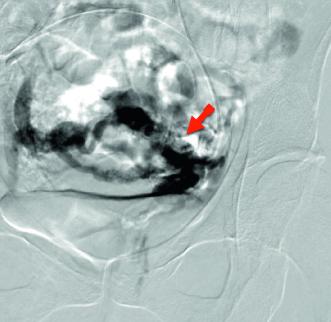

Typ Ovarialvene: Die Symptome des PCS werden durch insuffiziente Ovarialvenen hervorgerufen (Abb. 1). Dabei können einerseits insuffiziente Klappen der Vena ovarica zu einem Reflux führen und Krampfadern im kleinen Becken verursachen. Andererseits kann auch eine Einklemmung der linken Nierenvene (Nutcracker Anatomie) dazu führen, dass es zu einem Blutrückstau in die Eierstockvene und zu Krampfadern kommt. Nicht selten findet sich eine ­retroaortale Nierenvene oder eine Verengung der Vena cava inferior als Ursache der Ovarialveneninsuffizienz.

In unserer Anamnese der seit vielen Jahren bestehenden Unterbauchschmerzen zeigten sich lageabhängige Beschwerden, die im Tagesverlauf zunahmen und in die Leistengegend sowie den Oberschenkel ausstrahlten. Ergänzt wurde die Anamnese durch Feststellung einer Pollakisurie und Dyspareunie. In der angiologischen Diagnostik konnte mittels farbkodierter Duplexsonographie eine Nutcracker-Anatomie (Einklemmung der linken Nierenvene zwischen der oberen Darmarterie und der Bauchaorta) und eine May-Thurner-Anatomie (Kompression der linken Vena iliaca commuis durch die rechte Arteria iliaca communis) festgestellt werden (Abb. 4, 5). In der MR-Phlebographie fanden wir ausgeprägte parauterine Varizen und eine stark erweiterte insuffiziente Vena ovarica links (Abb. 6).

Bei typischen Pelvic Congestion-Symptomen und hohem Leidensdruck von Patientin S. B. entschieden wir uns nach ausführlicher Besprechung für ein minimal-invasives Vorgehen mit Embolisation der Vena ovarica links. Über einen jugulären Zugang wurde ein Katheter in die Ovarialvene eingelegt, worüber ein aufgeschäumtes Sklerosierungsmittel (Aethoxysklerol 3 %, 15 ml) zur Verödung der parauterinen Venen injiziert wurde. Anschliessend wurden der Patientin kleine Drahtspiralen (Coils) implantiert, um die Vena ovarica endgültig zu verschliessen (Abb. 7). S. B. konnte gleichentags im guten Allgemeinzustand nach Hause entlassen werden.